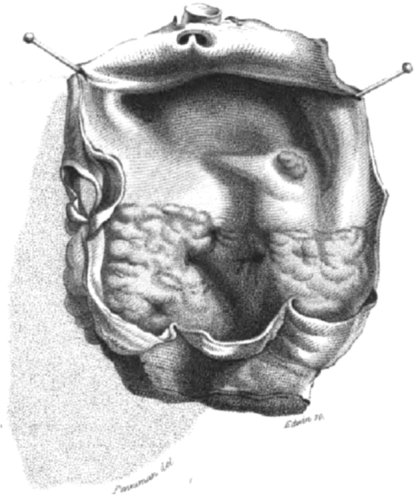

PLATE II.

Is a representation of the fleshlike thickening of the aorta in case 7th. The valves are smaller than usual, and their form is in some degree changed. A round spot, thickened, is seen at a little distance from the seat of the principal disease.